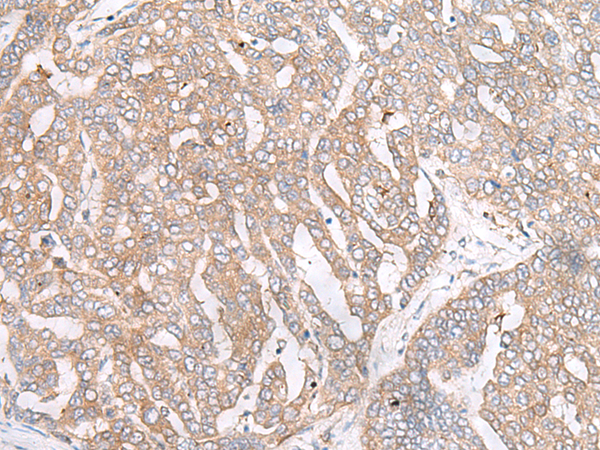

IHC positive control: |

Human liver cancer |

IHC Recommend dilution: |

50-300 |